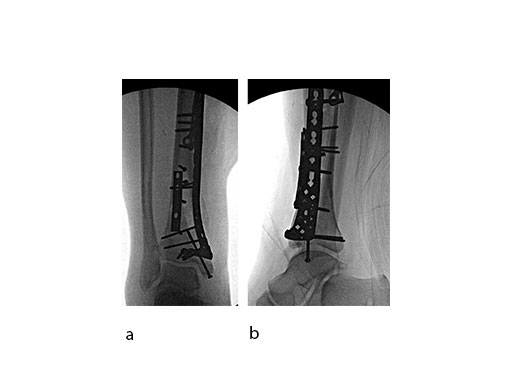

A 61-year-old laborer fell 5 meters from scaffolding. This was a closed injury with severe soft-tissue injury (Fig 67). He required three weeks of jointspanning external fixation prior to adequate resolution of edema.

Initial fixation was via a limited posteromedial exposure to buttress a posteromedial partial articular fragment (Fig 8). Following articular reduction and supplemental lateral column plate fixation via a limited anteromedial joint exposure, the VA-LCP Anteromedial Distal Tibia Plate was passed subcutaneous with subsequent percutaneous screw insertions into the plate shaft.

There was good maintenance of reduction at 5 weeks (Fig 9).